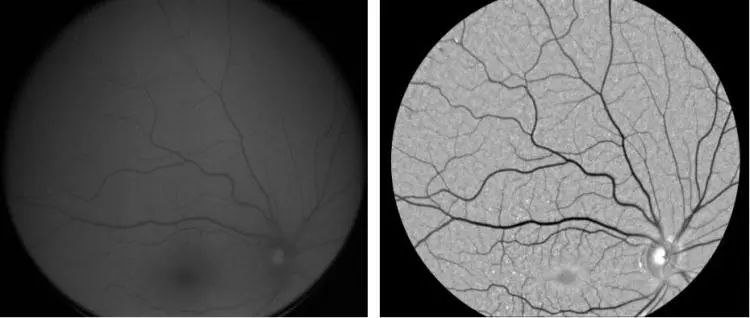

据 Neurovision的联合创始人Steven Verdoone表示,Neurovision的人工智能模型可以分析眼球扫描图像中的异常情况,比如某些蛋白质的堆积或形状扭曲的血管,而这些都与阿尔茨海默病有关。

当前人们很少能在体检扫描中发现这些迹象,许多扫描出来的图片都存在暗区。而且斑块沉积可能会非常小,仅靠人眼无法很好地进行识别。但在Verdoone看来,AI在这方面比人类表现得更好。

而有了 AI技术的支持,不仅诊断速度被加快了,还可以降低其成本。RetiSpec的AI技术可以帮助提取摄像头的扫描结果,这需要一种新型摄像头,目前已经被安装在许多验光诊所的设备上。

这种摄像头测量的光谱范围比人眼更广,让 AI可以检测出与大脑中淀粉样蛋白存在情况相对应的独特光学特征。最新的研究显示,通过对271名患者的调查,新技术检测到淀粉样蛋白的准确率达到了80%。